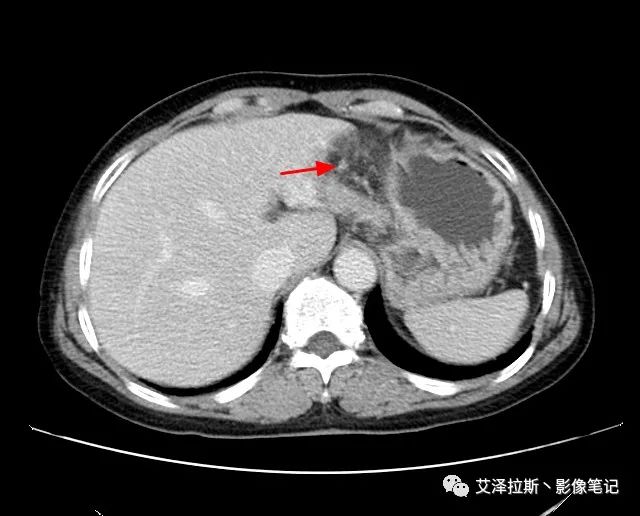

【影像所見】 胃竇部狹窄,胃壁環(huán)形增厚,小彎側(cè)見一巨大潰瘍,周圍伴“環(huán)堤征”,漿膜面不完整,胃周脂肪見網(wǎng)格狀條索影,病灶與肝臟左葉、胰腺鉤突脂肪間隙消失,增強(qiáng)掃描病灶明顯強(qiáng)化。引流區(qū)內(nèi)約15個區(qū)域淋巴結(jié)受累。

【診斷意見】 胃竇部胃癌(T4N3期) 該病例腫塊突破漿膜層,與肝臟左葉、胰腺鉤突分界不清,脂肪界面消失,定為T4期; 受累及的淋巴結(jié)為15個區(qū)域,定為N3; 有無遠(yuǎn)處轉(zhuǎn)移尚不明確,所以M期暫時無法確定。